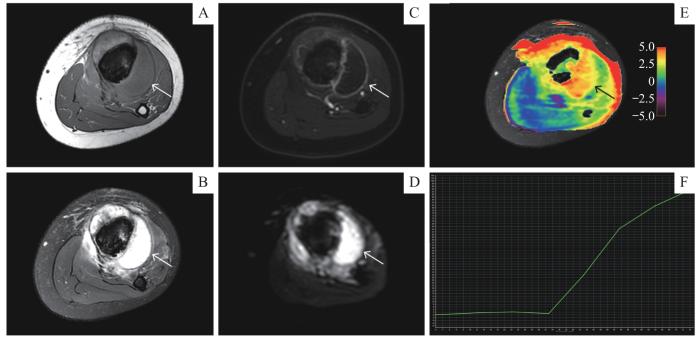

病例2,患者,男,12岁,左小腿疼痛3周余,以左侧胫骨恶性肿瘤收治入院,已完成4次顺铂和脂质体阿霉素的新辅助化疗方案。术前MRI增强检查结果( 图5)示左侧胫骨干骨质破坏,周围皮质破坏、形成软组织肿块,突破骺板,累及骨骺,肿瘤最大直径约18.92 cm。DCE-TIC曲线Ⅰ型,ADC值1.97×10 -3 mm 2/s,提示对化疗效果的评估有限。APTw成像测得APT值为3.67%,显著高于未化疗的恶性肿瘤参考值,提示肿瘤对化疗有反应。这表明APT值在化疗后有所回升,符合肿瘤细胞对化疗药物的敏感性( 图5E)。术后病理提示骨肉瘤化疗后改变,与APTw成像评估结果相符。

图5

图5   APTw成像在恶性骨肿瘤新辅助化疗中的应用

Note: A 12-year-old male with osteosarcoma in the left tibia showed chemotherapy-related changes. A. Axial T1-weighted MRI sequence. B. Axial T2-weighted fat-saturated MRI sequence. C. Axial contrast-enhanced T1-weighted MRI sequence. D. Axial DWI ( b=1 000 s·mm -2) sequence. E. Axial APT image fused with axial T2WI (the color bar indicates the APT values). F. TIC classification (type Ⅰ).

Fig 5   Application of APTw imaging in neoadjuvant chemotherapy for malignant bone tumor